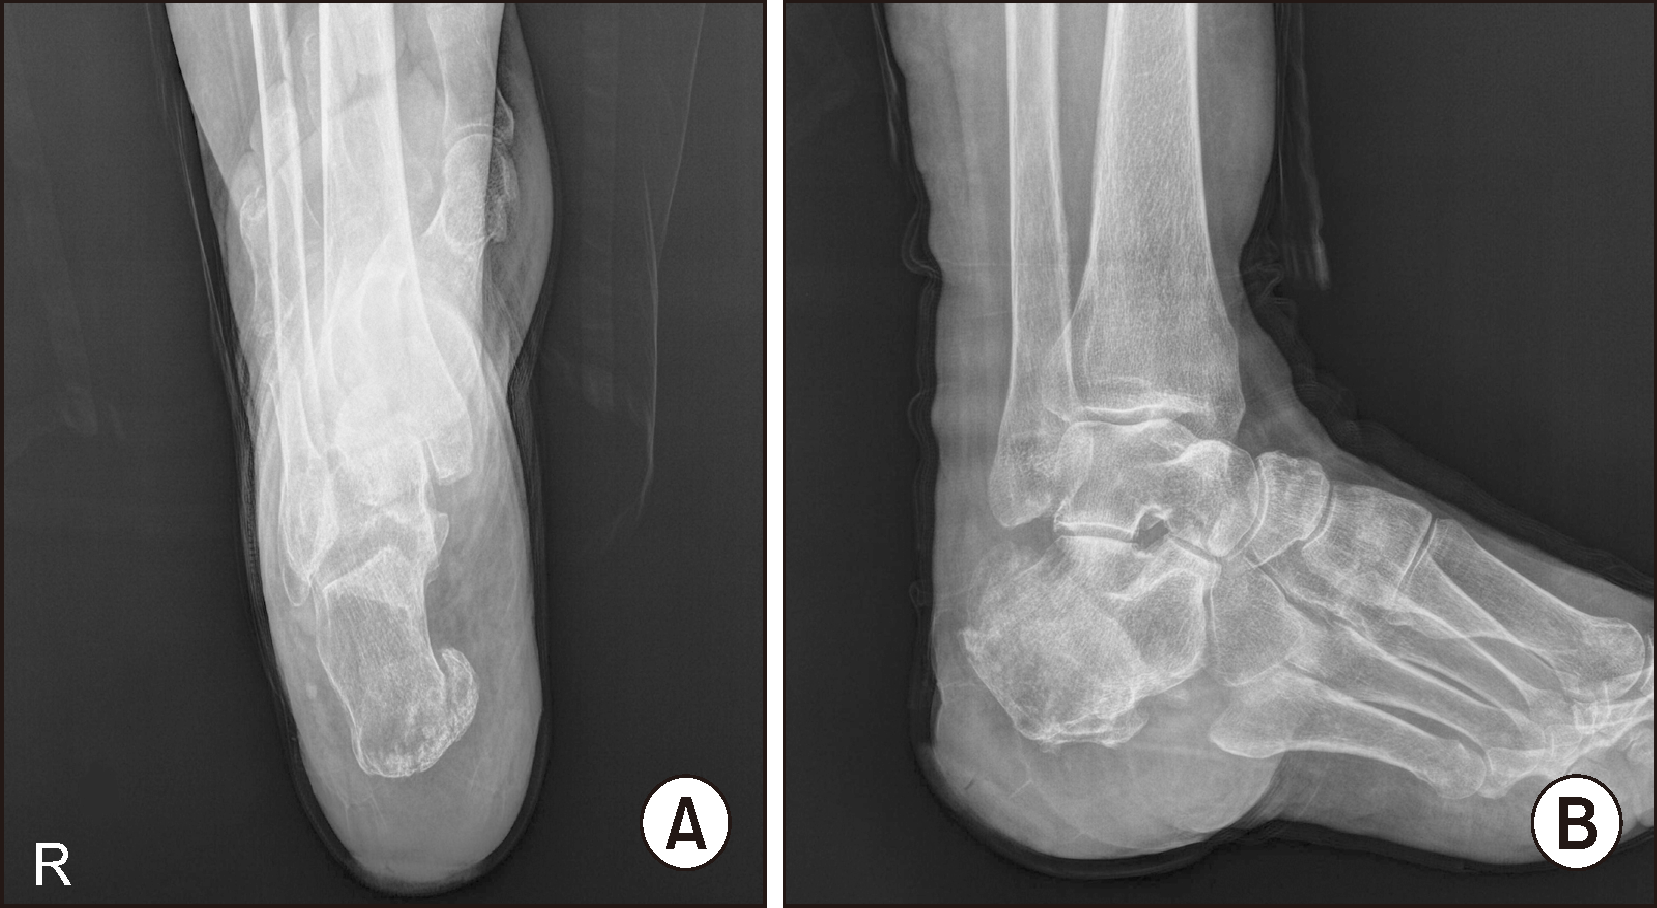

진찰상 우측 후족부에 3×3 cm의 궤양이 발견되었으며, 궤양을 통한 골노출은 없었다. 단순 방사선 검사에서 우측 종골의 골용해성 병변이 확인되었으며(Fig. 2), 족부 자기공명영상(magnetic resonance imaging, MRI) 검사에서 종골의 아급성 골절 및 골수 부종 소견(Fig. 3), 3상 골 스캔 (3 phase bone scan) 검사의 지연 영상(delayed phase)에서 종골에 국한된 강한 섭취를 보여(hot uptake) (Fig. 4), 종골의 만성 골수염으로 진단하였다.

Figure 2

The initial radiographs of right foot (A, B). Osteolytic lesion and deformity of calcaneus are visible.